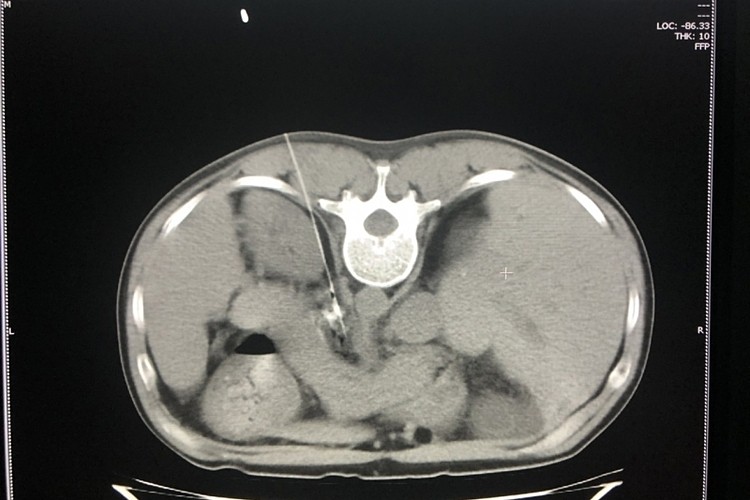

Bác sĩ Lê Tiến Hưng, Phó Trưởng Khoa Chẩn đoán hình ảnh, thực hiện kỹ thuật diệt đám rối thần kinh thân tạng, giảm đau cho bệnh nhân.

Bệnh nhân không cần gây mê. Các bác sĩ tiêm cồn tuyệt đối diệt hạch thân tạng, dưới hướng dẫn của kỹ thuật cắt lớp vi tính. Yêu cầu đường kim chọc vào đám rối thân tạng phải chính xác tuyệt đối, tránh làm tổn thương gan, tạng, chọc thủng tạng hoặc mạch máu trong quá trình can thiệp.